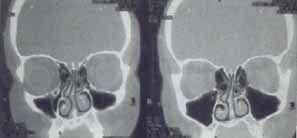

Figura 12. Tomografía computarizada con desviación septal derecha y mucocele maxilo etmoidal contralateral.

Figura 14. Tomografía computarizada practicada a paciente con septoplastia previa, con obstrucción nasal a predominio derecho, secreción posnasal y cefaleas persistentes, a pesar de la cirugía. En ella además, de observar una desviación septal de la lámina perpen-dicular del etmoides, se aprecian cornetes medios bulosos, cornetes inferiores asimétricamente resecados y engrosamiento mucoso etmoidal.